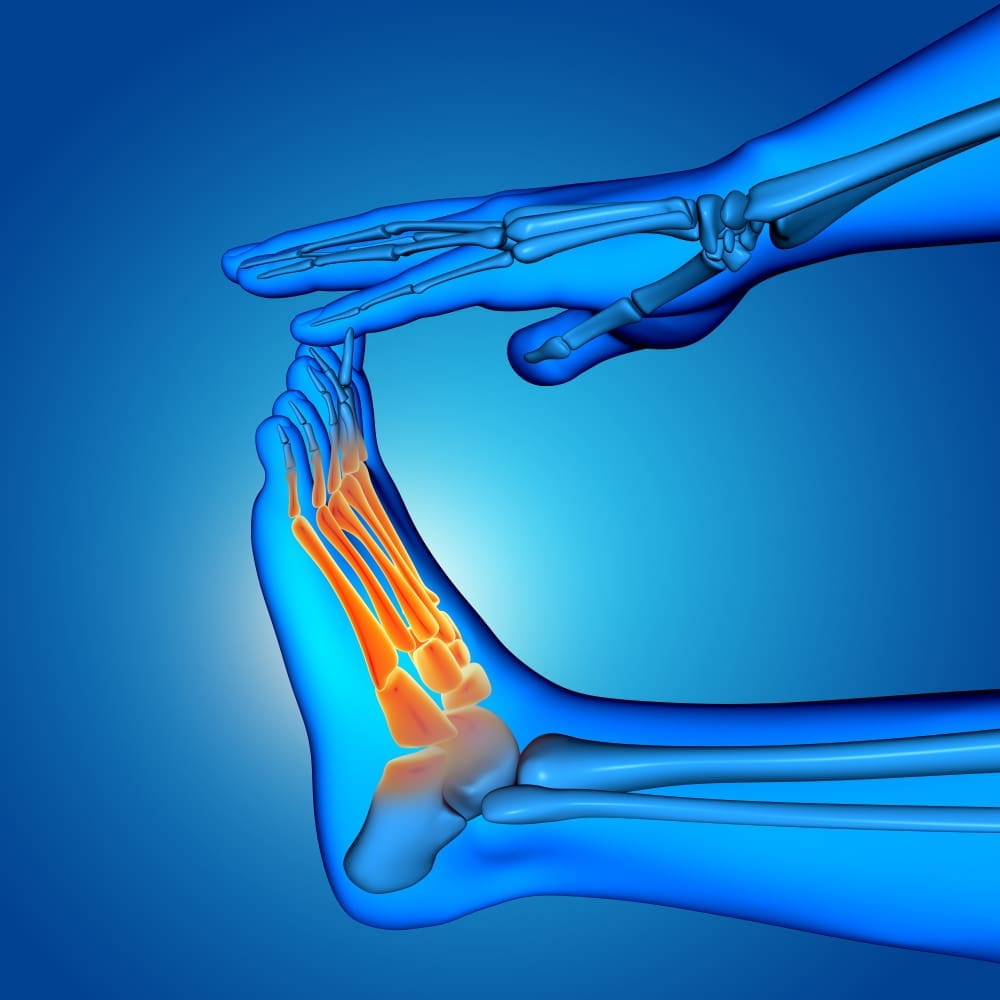

تتمتع بعض العظام، مثل عظام القدم، بثبات جوهري ممتاز وإمداد بالدم، وفي هذه الحالة يمكن أن تلتئم حتى مع العلاج غير الجراحي والحد الأدنى من الاستقرار.

في بعض العظام، مثل رأس الفخذ أو الزورق في الرسغ، يمكن أن تتسبب الكسور في تمزق الأوعية الدموية، لذلك هناك خطر كبير للإصابة بداء المفصل الكاذب.

بعض العظام، مثل قصبة الساق، لديها إمدادات دم غير كافية ؛ الصدمات يمكن أن تضعف حالة الجلد وتعزز التهاب المفاصل الكاذب في المنطقة.